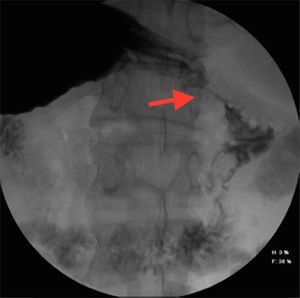

A 57-year-old man with an unremarkable past medical history complained of moderately intense localized pain in the epigastrium after eating solid foods, and later after drinking liquids. The accompanying nausea and vomiting caused important fluid and electrolyte imbalance, for which he was hospitalized. Laboratory tests and imaging studies were ordered and chronic cholecystitis with gallstones was diagnosed through ultrasound imaging (USG). A lesion infiltrating into the first portion of the duodenum and an ulcer were identified at endoscopy and at esophagogastroduodenography (EGD) (fig. 1). A computed axial tomography scan showed gas in the gallbladder and thickening of the gastric antrum and the duodenal bulb walls (figs. 2 and 3). Tumor markers were in the normal range. The patient underwent exploratory laparotomy that revealed chronic inflammation of the gall bladder, cholecystoduodenal fistula with loss of the normal anatomic arrangement, and annular pancreas (figs. 4 and 5) that did not compromise the integrity or permeability of the duodenum. Cholecystectomy was performed, the fistula was dismantled, and primary closure of the duodenum was carried out. The patient progressed favorably and is currently under follow-up at the hepatopancreaticobiliary surgery clinic.